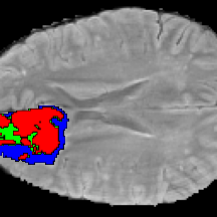

Current research on deep learning for medical image segmentation exposes their limitations in learning either global semantic information or local contextual information. To tackle these issues, a novel network named SegTransVAE is proposed in this paper. SegTransVAE is built upon encoder-decoder architecture, exploiting transformer with the variational autoencoder (VAE) branch to the network to reconstruct the input images jointly with segmentation. To the best of our knowledge, this is the first method combining the success of CNN, transformer, and VAE. Evaluation on various recently introduced datasets shows that SegTransVAE outperforms previous methods in Dice Score and $95\%$-Haudorff Distance while having comparable inference time to a simple CNN-based architecture network. The source code is available at: https://github.com/itruonghai/SegTransVAE.